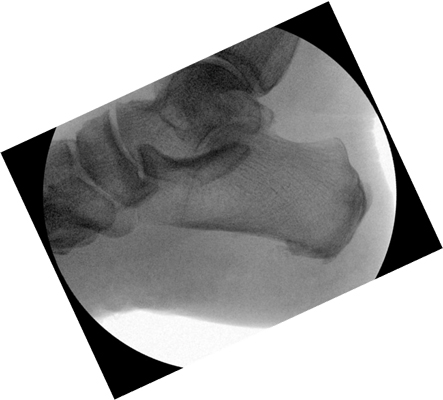

TOTAL ANKLE REPLACEMENT :: ORIF CALCANEUS :: ORIF ANKLE FRACTURE DISLOCATION :: COMPLEX BUNION AND LESSER TOE CORRECTION :: TALUS FRACTURE -1 :: TALUS FRACTURE -2 :: LISFRANC REPAIR :: COMPLEX TRIPLE ARTHRODESIS 1 :: COMPLEX TRIPLE ARTHRODESIS 2 :: MINIMALLY INVASIVE BUNION REPAIR 1 :: MINIMALLY INVASIVE BUNION REPAIR 2 :: ARTHROSCOPIC CARTILAGE REPAIR :: TENEX SPUR DEBRIDEMENT :: Haglunds Debridement and Achilles Repair